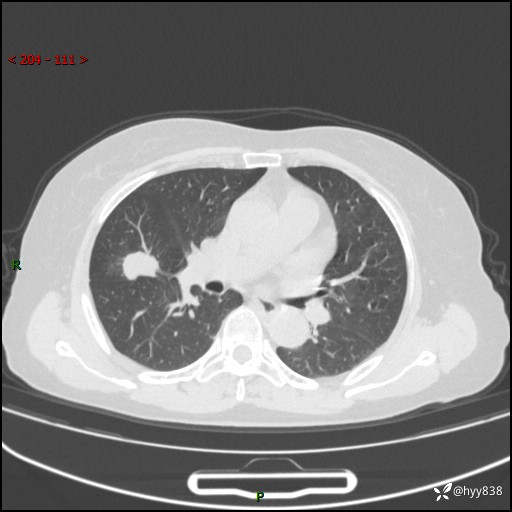

现病史:患者1月前无明显诱因出现痰中带鲜红色血丝,伴间断咳嗽,晨起明显,无胸闷、胸痛,无恶心、呕吐,无发热、畏寒,无活动后气短,无盗汗、咯血、消瘦等不适,未行诊疗。患者1天前于我院就诊,行胸部CT:右肺中叶及右肺下叶结节影,右肺上叶磨玻璃影,左肺上叶纤维灶。门诊以“咯血原因待查 肺结节”收入我科。 起病以来,患者精神、饮食、睡眠尚可,大小便正常,体力、体重未见明显改变。

胸部CT平扫+增强